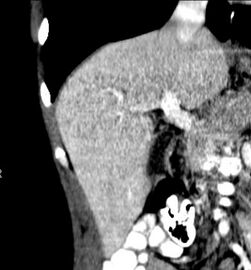

صورة مقطعية محورية تظهر أوردة كبدية شاذة تنتشر على السطح الأمامي تحت المحفظة للكبد.[73]